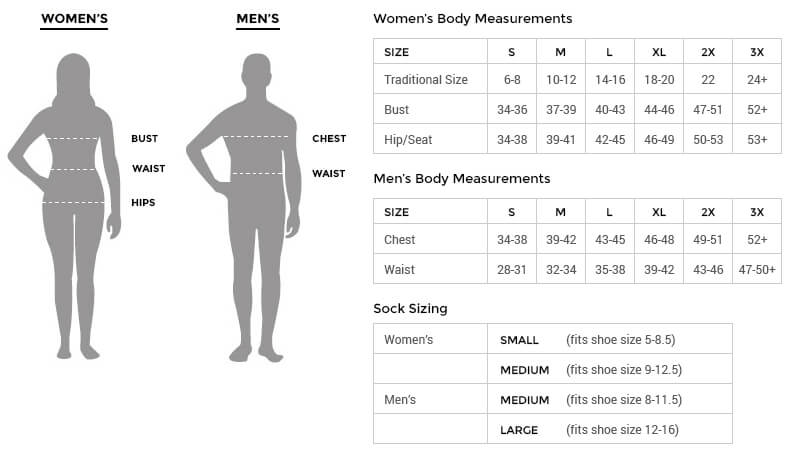

Immunohistochemistry analysis of paraffin embedded human colon cancer using P-α-tubulin (GB14162) at dilution of 1: 200 |